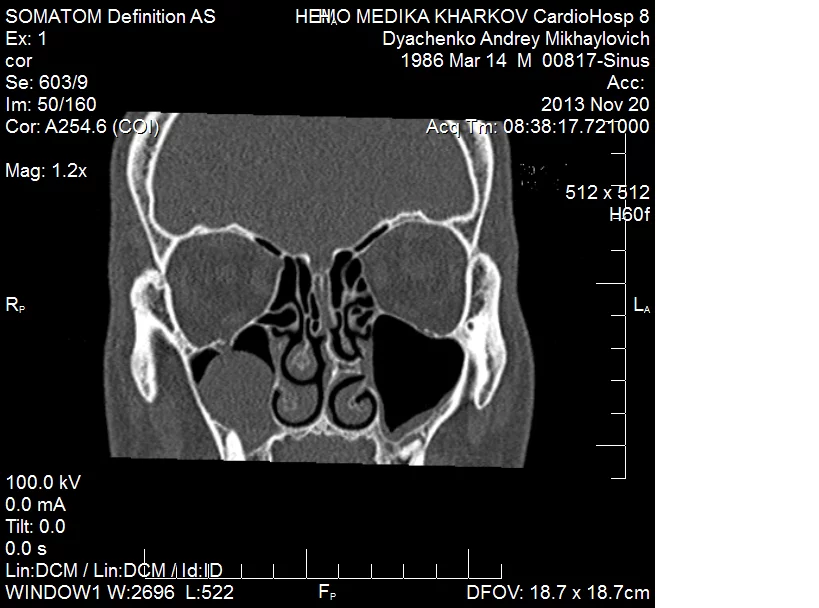

А можно дурной вопрос? Если нос не беспокоит, но снимок подобен тому что у Dyak, пазуха заполнена полностью, обязательно ли лезть туда? Просто обнаружилась эта "красота" внезапно на панорамном снимке для стоматолога, который говорит, что нужно обязательно к ЛОРу...

Подскажите плиз насколько необходима гйморотомия если киста абсолютно не беспокоит.